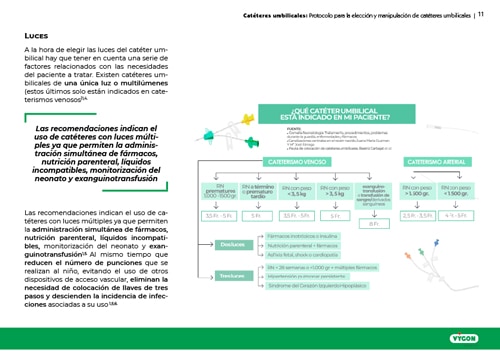

El uso del cateterismo umbilical es una práctica usual en las unidades de cuidados intensivos neonatales. Su aplicación en la atención a recién nacidos ha ido variando y ajustándose a las demandas de los pacientes y al desarrollo de nuevas tecnologías y procedimientos en el campo de los cuidados neonatales.